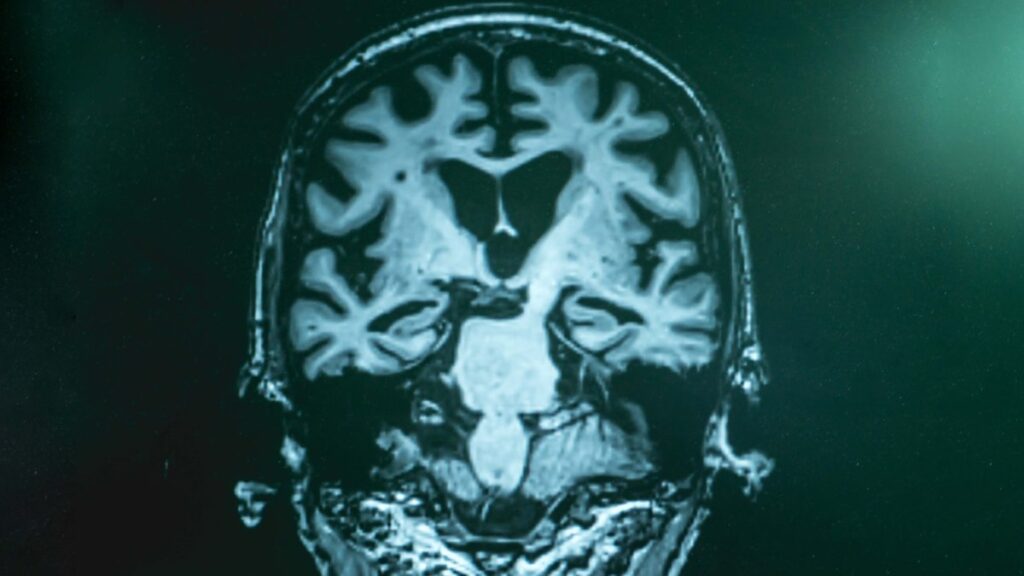

BARCELONA, España – Un equipo internacional liderado por investigadores de la Fundación española Pasqual Maragall ha corroborado, en un estudio con una amplia cohorte y biomarcadores, la relación entre mala calidad del sueño y un mayor riesgo de desarrollar alzhéimer en personas sin deterioro cognitivo.

Para este estudio, hecho público este jueves, se ha empleado la cohorte más grande hasta la fecha (el estudio europeo de cohortes longitudinales para prevención de la demencia por alzhéimer) y se han añadido unos biomarcadores de líquido cefalorraquídeo, que predicen incrementos futuros de la patología en personas sin síntomas identificables de la enfermedad de Alzheimer.

En concreto, el equipo del BBRC, en colaboración con investigadores de la Universidad de Bristol (Reino Unido), ha analizado los datos de 1,168 adultos mayores de 50 años, incluyendo biomarcadores de la enfermedad de Alzheimer en el líquido cefalorraquídeo, rendimiento cognitivo y calidad del sueño.

Mediante el análisis de muestras de líquido cefalorraquídeo de 332 participantes tomadas al inicio y después de un período promedio de 1.5 años, los investigadores han podido evaluar el efecto de la calidad del sueño inicial sobre el cambio en los biomarcadores del mal de Alzheimer a lo largo del tiempo.

Entre otros hallazgos, se ha demostrado que una duración corta del sueño, inferior a siete horas, se asocia con valores más altos de proteínas tau, biomarcadores clave para medir el riesgo de Alzheimer en la fase preclínica, es decir, antes de la aparición de los síntomas de la enfermedad.